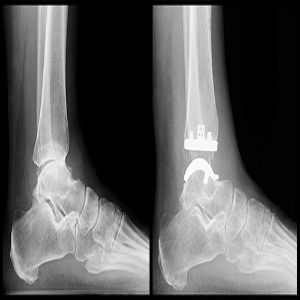

We Provide Best Doctor For Ankle Replacement Surge...